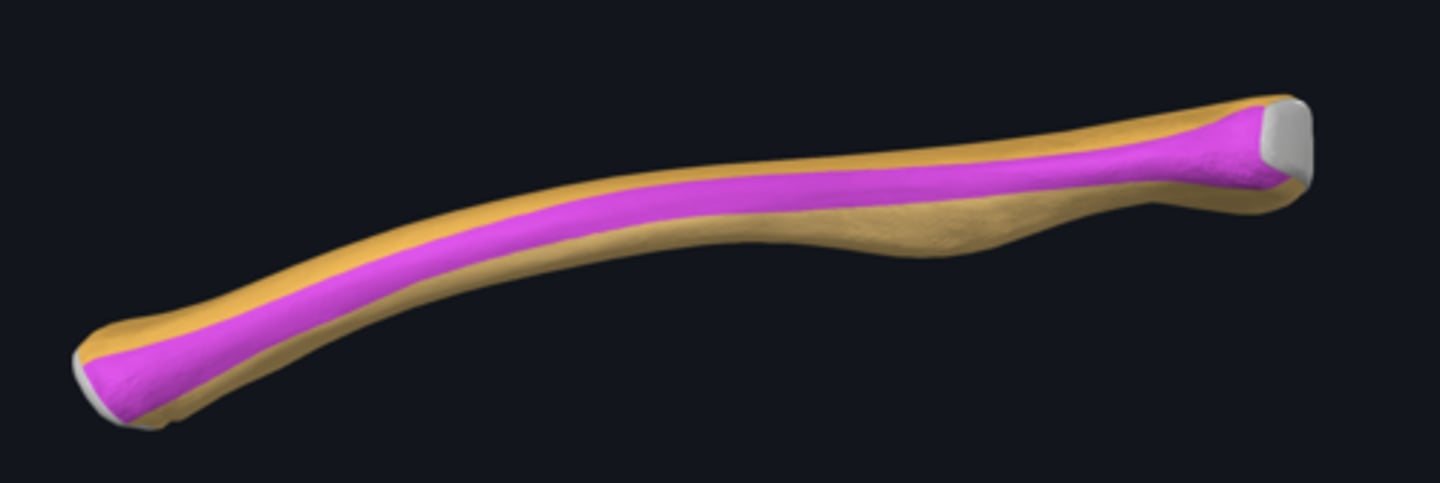

bones of the upper limb

body of ulna

distal part of ulna

proximal part of ulna

anterior border of ulna

anterior surface of ulna

interosseous border of ulna

medial surface of ulna

posterior border of ulna

posterior surface of ulna

supinator crest

anterior border of radius

anterior surface of radius

carpal articular surface

interosseous border of radius

lateral surface of radius

posterior border of radius

posterior surface of radius